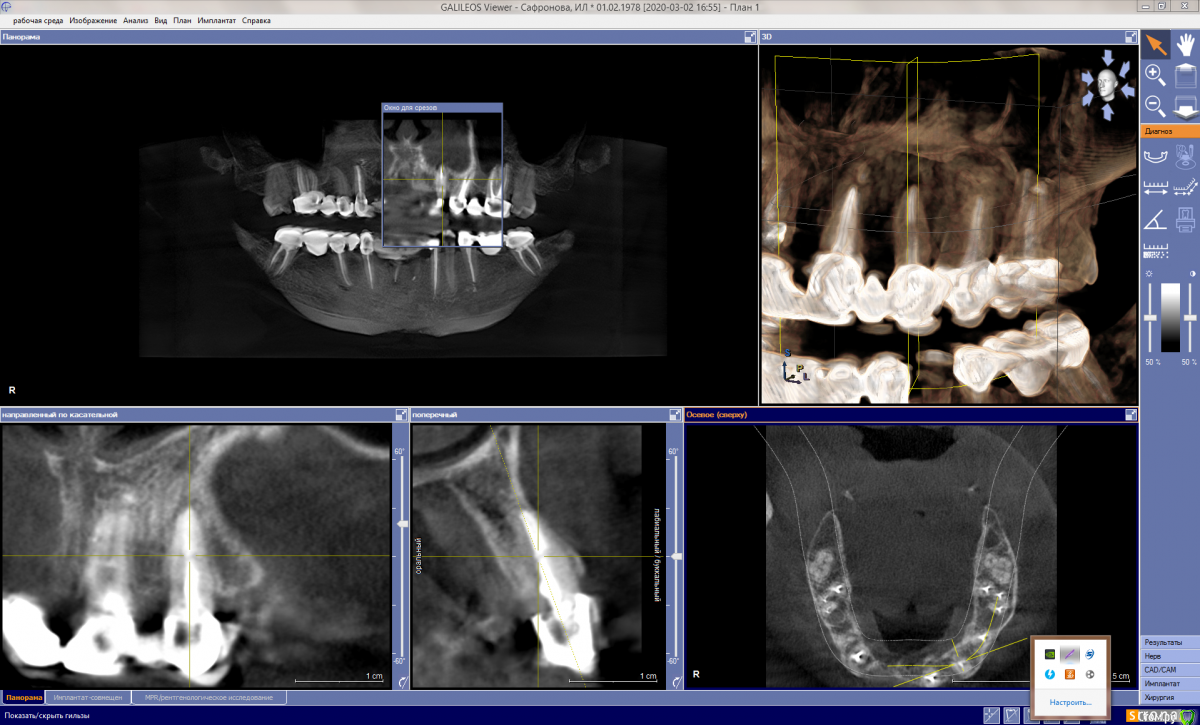

It'sGeorgy Опубликовано 12 мая, 2020 Поделиться Опубликовано 12 мая, 2020 (изменено) ну если прямо сильно нажимаю на него то ощющение небольшой боли вроде есть, а так кушать не больно им, а что скажите по кт, я в срезах не понимаюНа КТ, действительно, есть очаг разрежения костной ткани вокруг этого зуба. При этом, сказать, что каналы запломбированы плохо - тоже нельзя. Я не терапевт, но со своей точки зрения вижу ситуацию так, что у зуба, на самой вершине, есть достаточно выраженный изгиб, что создало огромную трудность для доктора, который зуб лечил. Этот изгиб, к сожалению, запломбировать ко конца не получилось, что привело к развитию хронического воспаления.Повторюсь, я подобным лечением не занимаюсь и мое мнение может быть ошибочным. Поэтому, предлагаю подождать, пока вам ответит кто-то из здешних терапевтов. это не может быть от зуба?Такие ситуации могут быть от зуба, но тогда боль острая и постоянная. Плюс, тогда пациент сам может определить, что его беспокоит конкретный зуб. В вашем случае, как я понимаю, такого нет. Да и судя по снимку, остальные верхние зубы слева в порядке. делала кт 3 раза за годЕсли есть возможность, выкладывайте их тоже. Потому, что на снимке, который вы выложили очень много фоновых шумов, которые создают металлические конструкции во рту(мостовидные протезы). Возможно, по снимкам до изготовления постоянных конструкций будет видно и понятно лучше. Изменено 12 мая, 2020 пользователем It'sGeorgy Ссылка на комментарий

It'sGeorgy Опубликовано 13 мая, 2020 Поделиться Опубликовано 13 мая, 2020 (изменено) Скажите а штифт не помешает для ретроградного пломбирования, или его надо как то убирать? Штифт ставится не на всю длину канала, поэтому вряд ли он помешает. Выделил его красным на прикрепленном снимке. я нашла кт за март 2019 года, сейчас дам вам ссылку, это до протезирования. Сохраните этот снимок куда-нибудь отдельно, чтобы не потерять его. Он четче и информативнее. Изменено 13 мая, 2020 пользователем It'sGeorgy Ссылка на комментарий

ira. k.. 78 Опубликовано 13 мая, 2020 Автор Поделиться Опубликовано 13 мая, 2020 Штифт ставится не на всю длину канала, поэтому вряд ли он помешает. Выделил его красным на прикрепленном снимке. Спасибо доктор. Это у меня киста или что это? Сохраните этот снимок куда-нибудь отдельно, чтобы не потерять его. Он четче и информативнее. Ссылка на комментарий